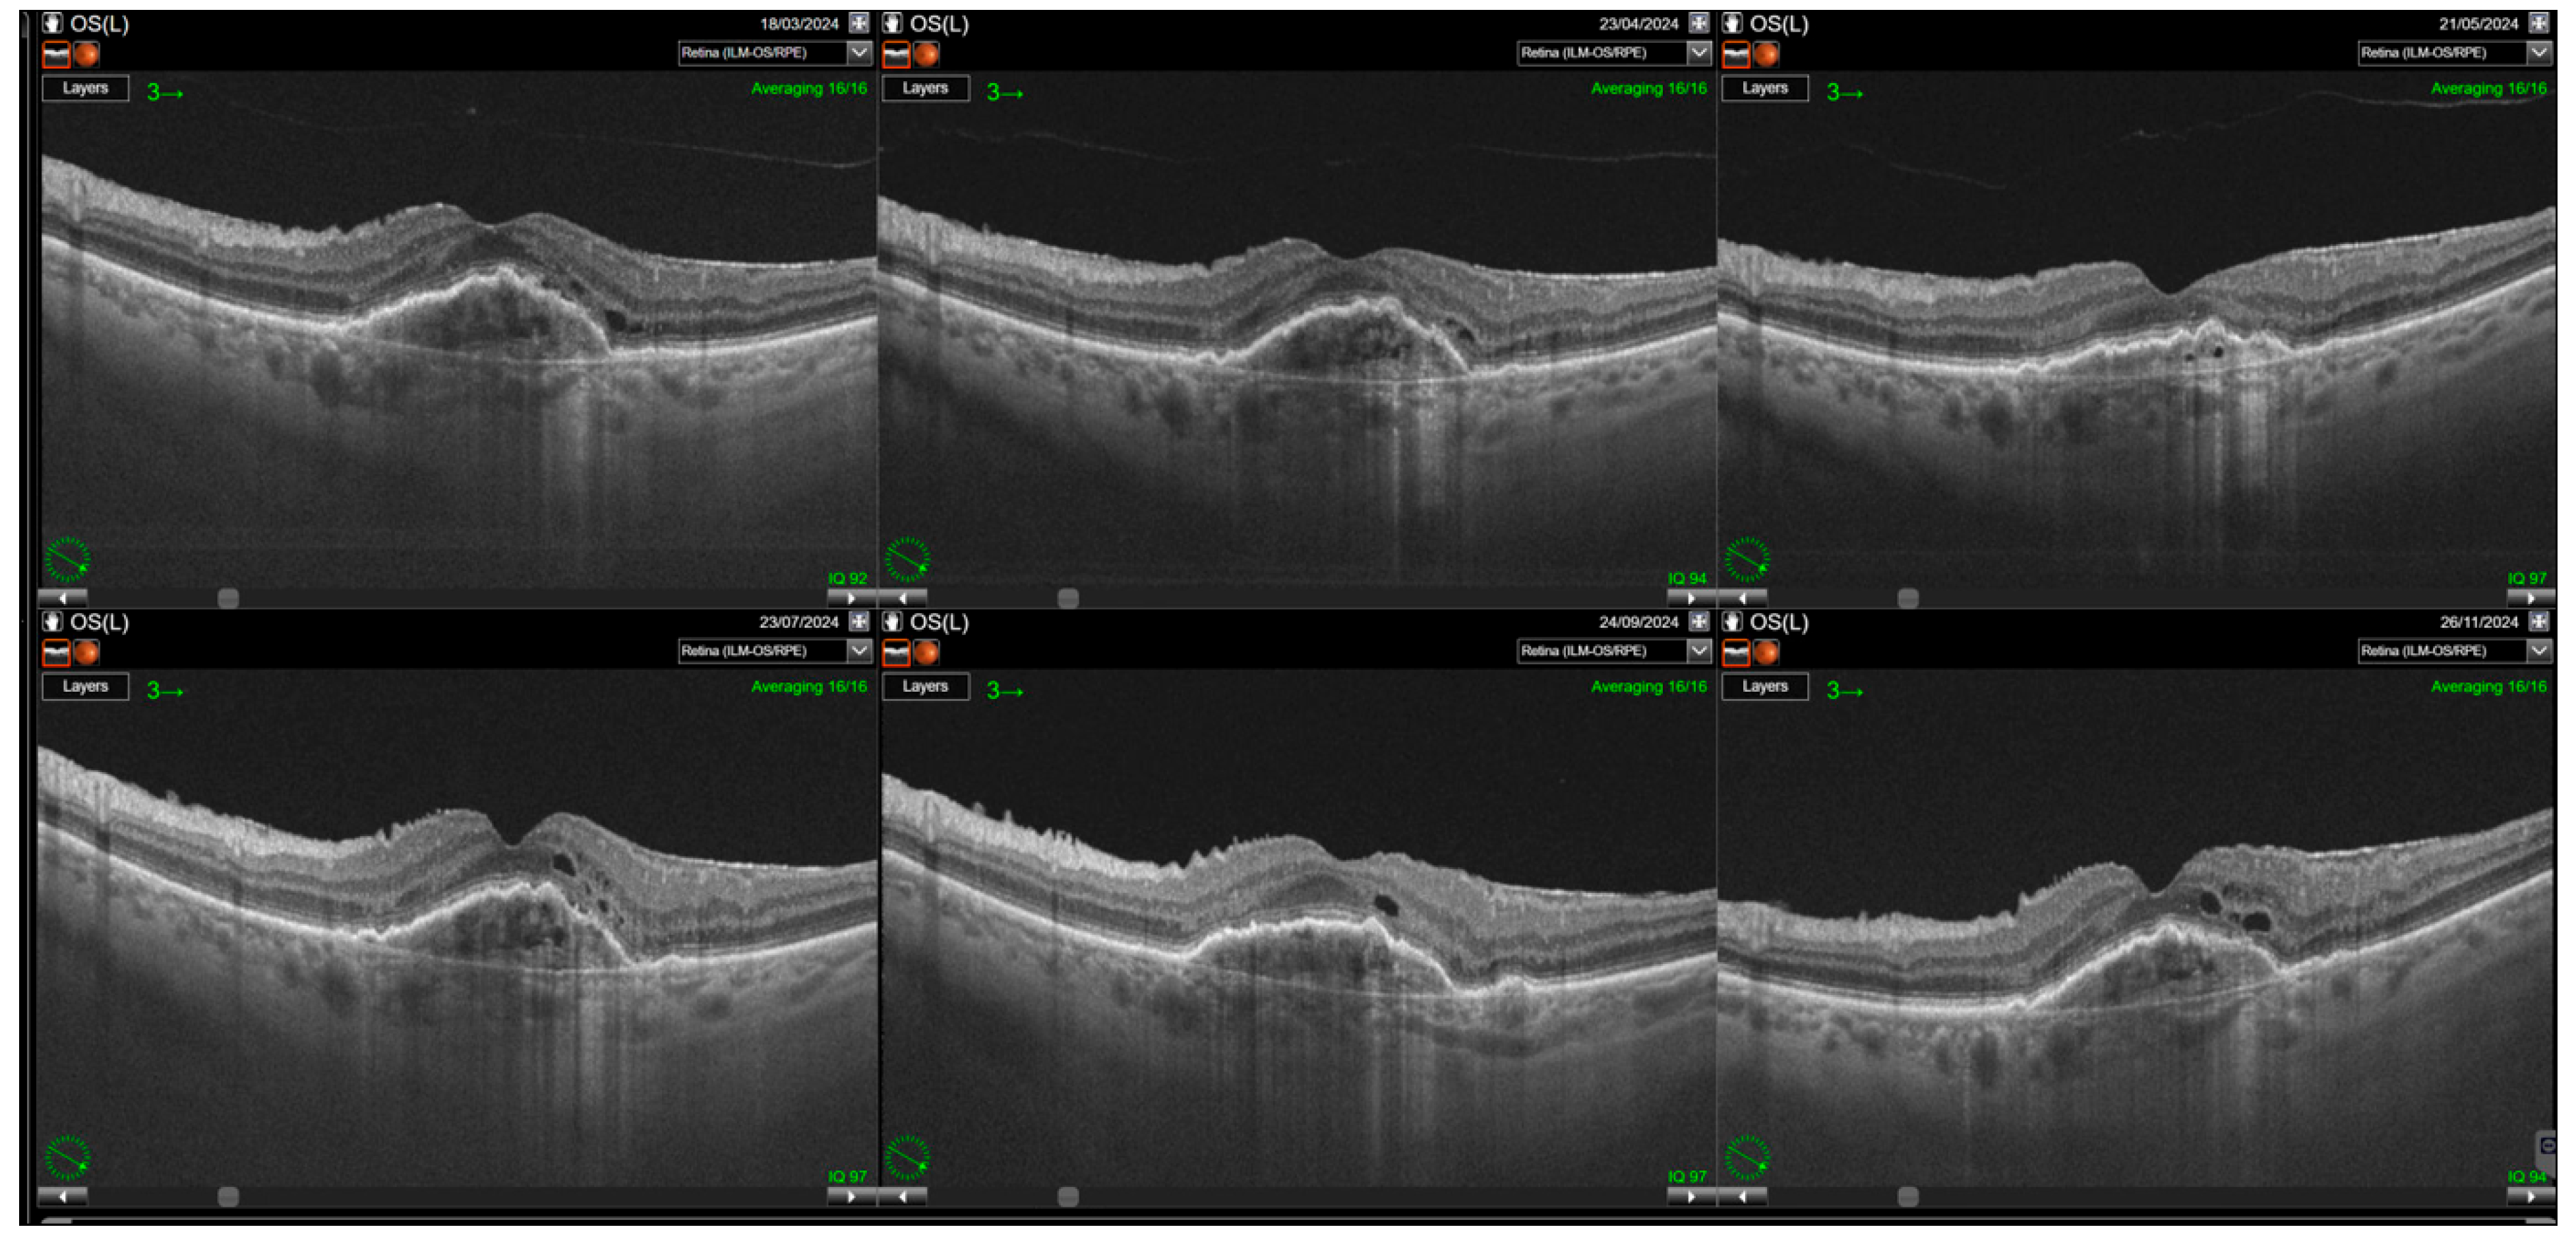

Switching to faricimab in the treatment of nAMD produced anatomical improvements that followed a distinct temporal pattern during post-switch follow-up. By the end of the observation period, retinal morphology demonstrated clear improvement, driven primarily by a reduction in SRF. In contrast, changes in IRF were not statistically significant, while reductions in PED reached borderline statistical significance at the final visit (p = 0.0455). The greatest morphological benefit was observed at visits 2 and 3, corresponding to the second phase of the loading regimen, during which the reduction in residual IRF was also statistically meaningful. However, as treatment intervals were subsequently extended, the magnitude of these anatomical gains gradually declined (Table 2). Loss of early improvement after the loading phase was also evident in SS-OCT parameters, specifically CST (Table 3; Figure 1). Retinal thickness showed a significant reduction compared with baseline during the loading phase, but this benefit gradually waned and was no longer present at the end of follow-up. Examples of SS-OCT scans at baseline and through the follow-up are presented in Figure 2 (good response) and Figure 3 and Figure 4 (poor response).

Figure 3. Relapse of intraretinal fluid after the loading phase. Resolution of intraretinal fluid (IRF) is achieved following the loading phase of treatment; however, IRF reappears with the extension of treatment intervals. Some cystic spaces visible on the scans correspond to neurodegenerative changes (collared, round retinal tubulations). Nevertheless, a significant increase in small intraretinal cystic lesions reflecting disease activity is also observed.